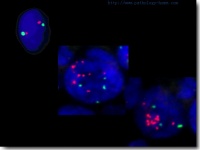

有一些家族内肾癌,在进行染色体检查时发现。肾癌高发生率的人中第三对染色体上有缺陷。多数家族性肾癌发病年龄比较早 , 趋于多病灶和双侧性。有一种罕见的遗传性疾病——遗传性斑痞性错构瘤 (VHP) 病的患者发生肾癌者多达 28%~45% 。